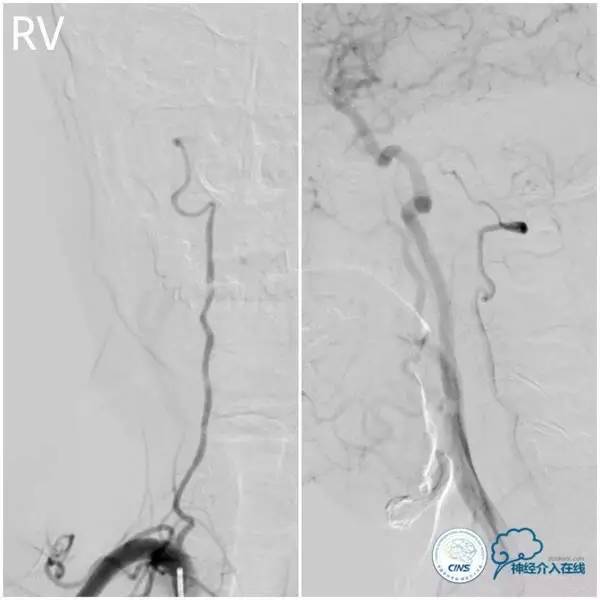

头颅CTA示基底动脉重度狭窄(图2)。

图2

术前造影(图3-6):左椎动脉优势,左椎动脉V4段迂曲,基底动脉近段重度狭窄,双侧胚胎型大脑后动脉。